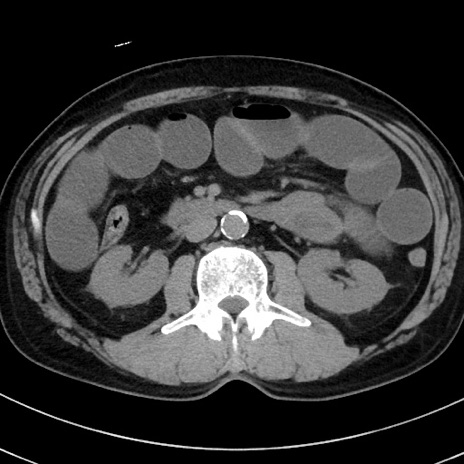

症例38(横断像)

冠状断像

【症例】70歳代 男性

【主訴】腹痛・嘔吐

【現病歴】昨晩より、嘔吐・腹痛あり。今朝になっても嘔吐あり。来院。

【既往歴】心臓バイパス手術、開腹胆摘、腸閉塞

【身体所見】BP 107/71mmHg、HR 116/min、腹部:平坦、軟、下腹部に軽度圧痛あり。反跳痛なし。

【データ】WBC 15100、CRP 0.32